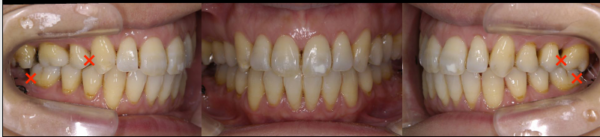

矯正終了時の状態です。ここから、メンテナンスに移行しました。

そして、治療終了後20年の状態です。

患者さまは還暦を迎えられましたが、お口の中は非常に健康で若々しい状態を保っておられます。